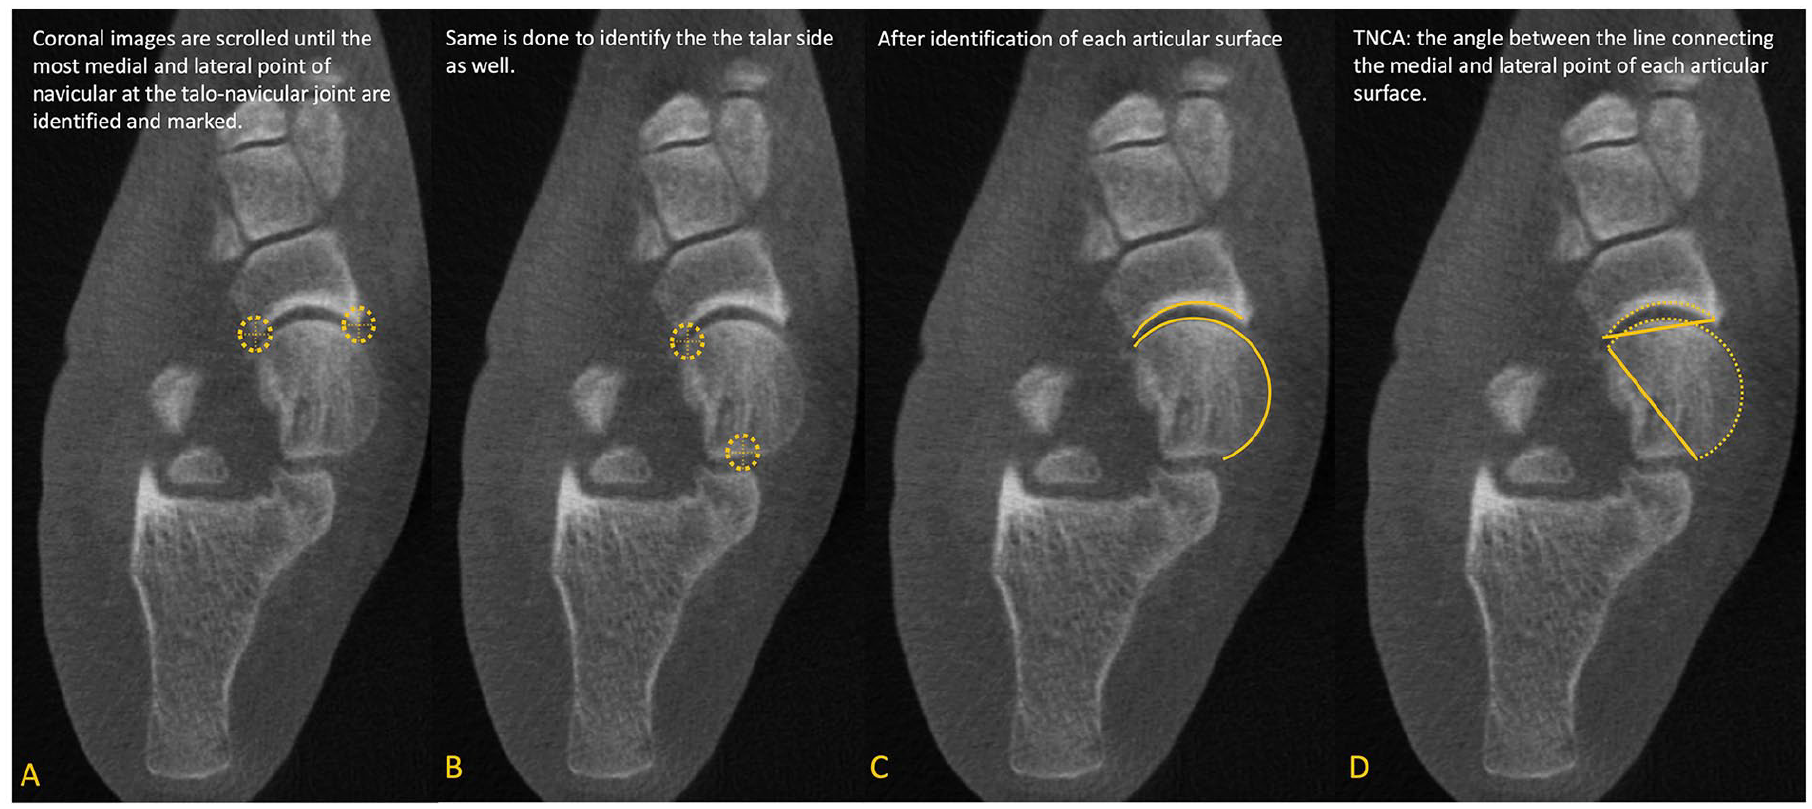

Talonavicular coverage angle (TNCA). On the axial view, (A) Marking medial and lateral edges of the proximal navicular articular surface. (B) Marking medial and lateral edges of the talar head articular surface. (C) Full proximal navicular and talar head articular surfaces highlighted. (D) Talonavicular Coverage Angle marked, with lines connecting medial and lateral edges of the proximal navicular and talar head articular surfaces. 34